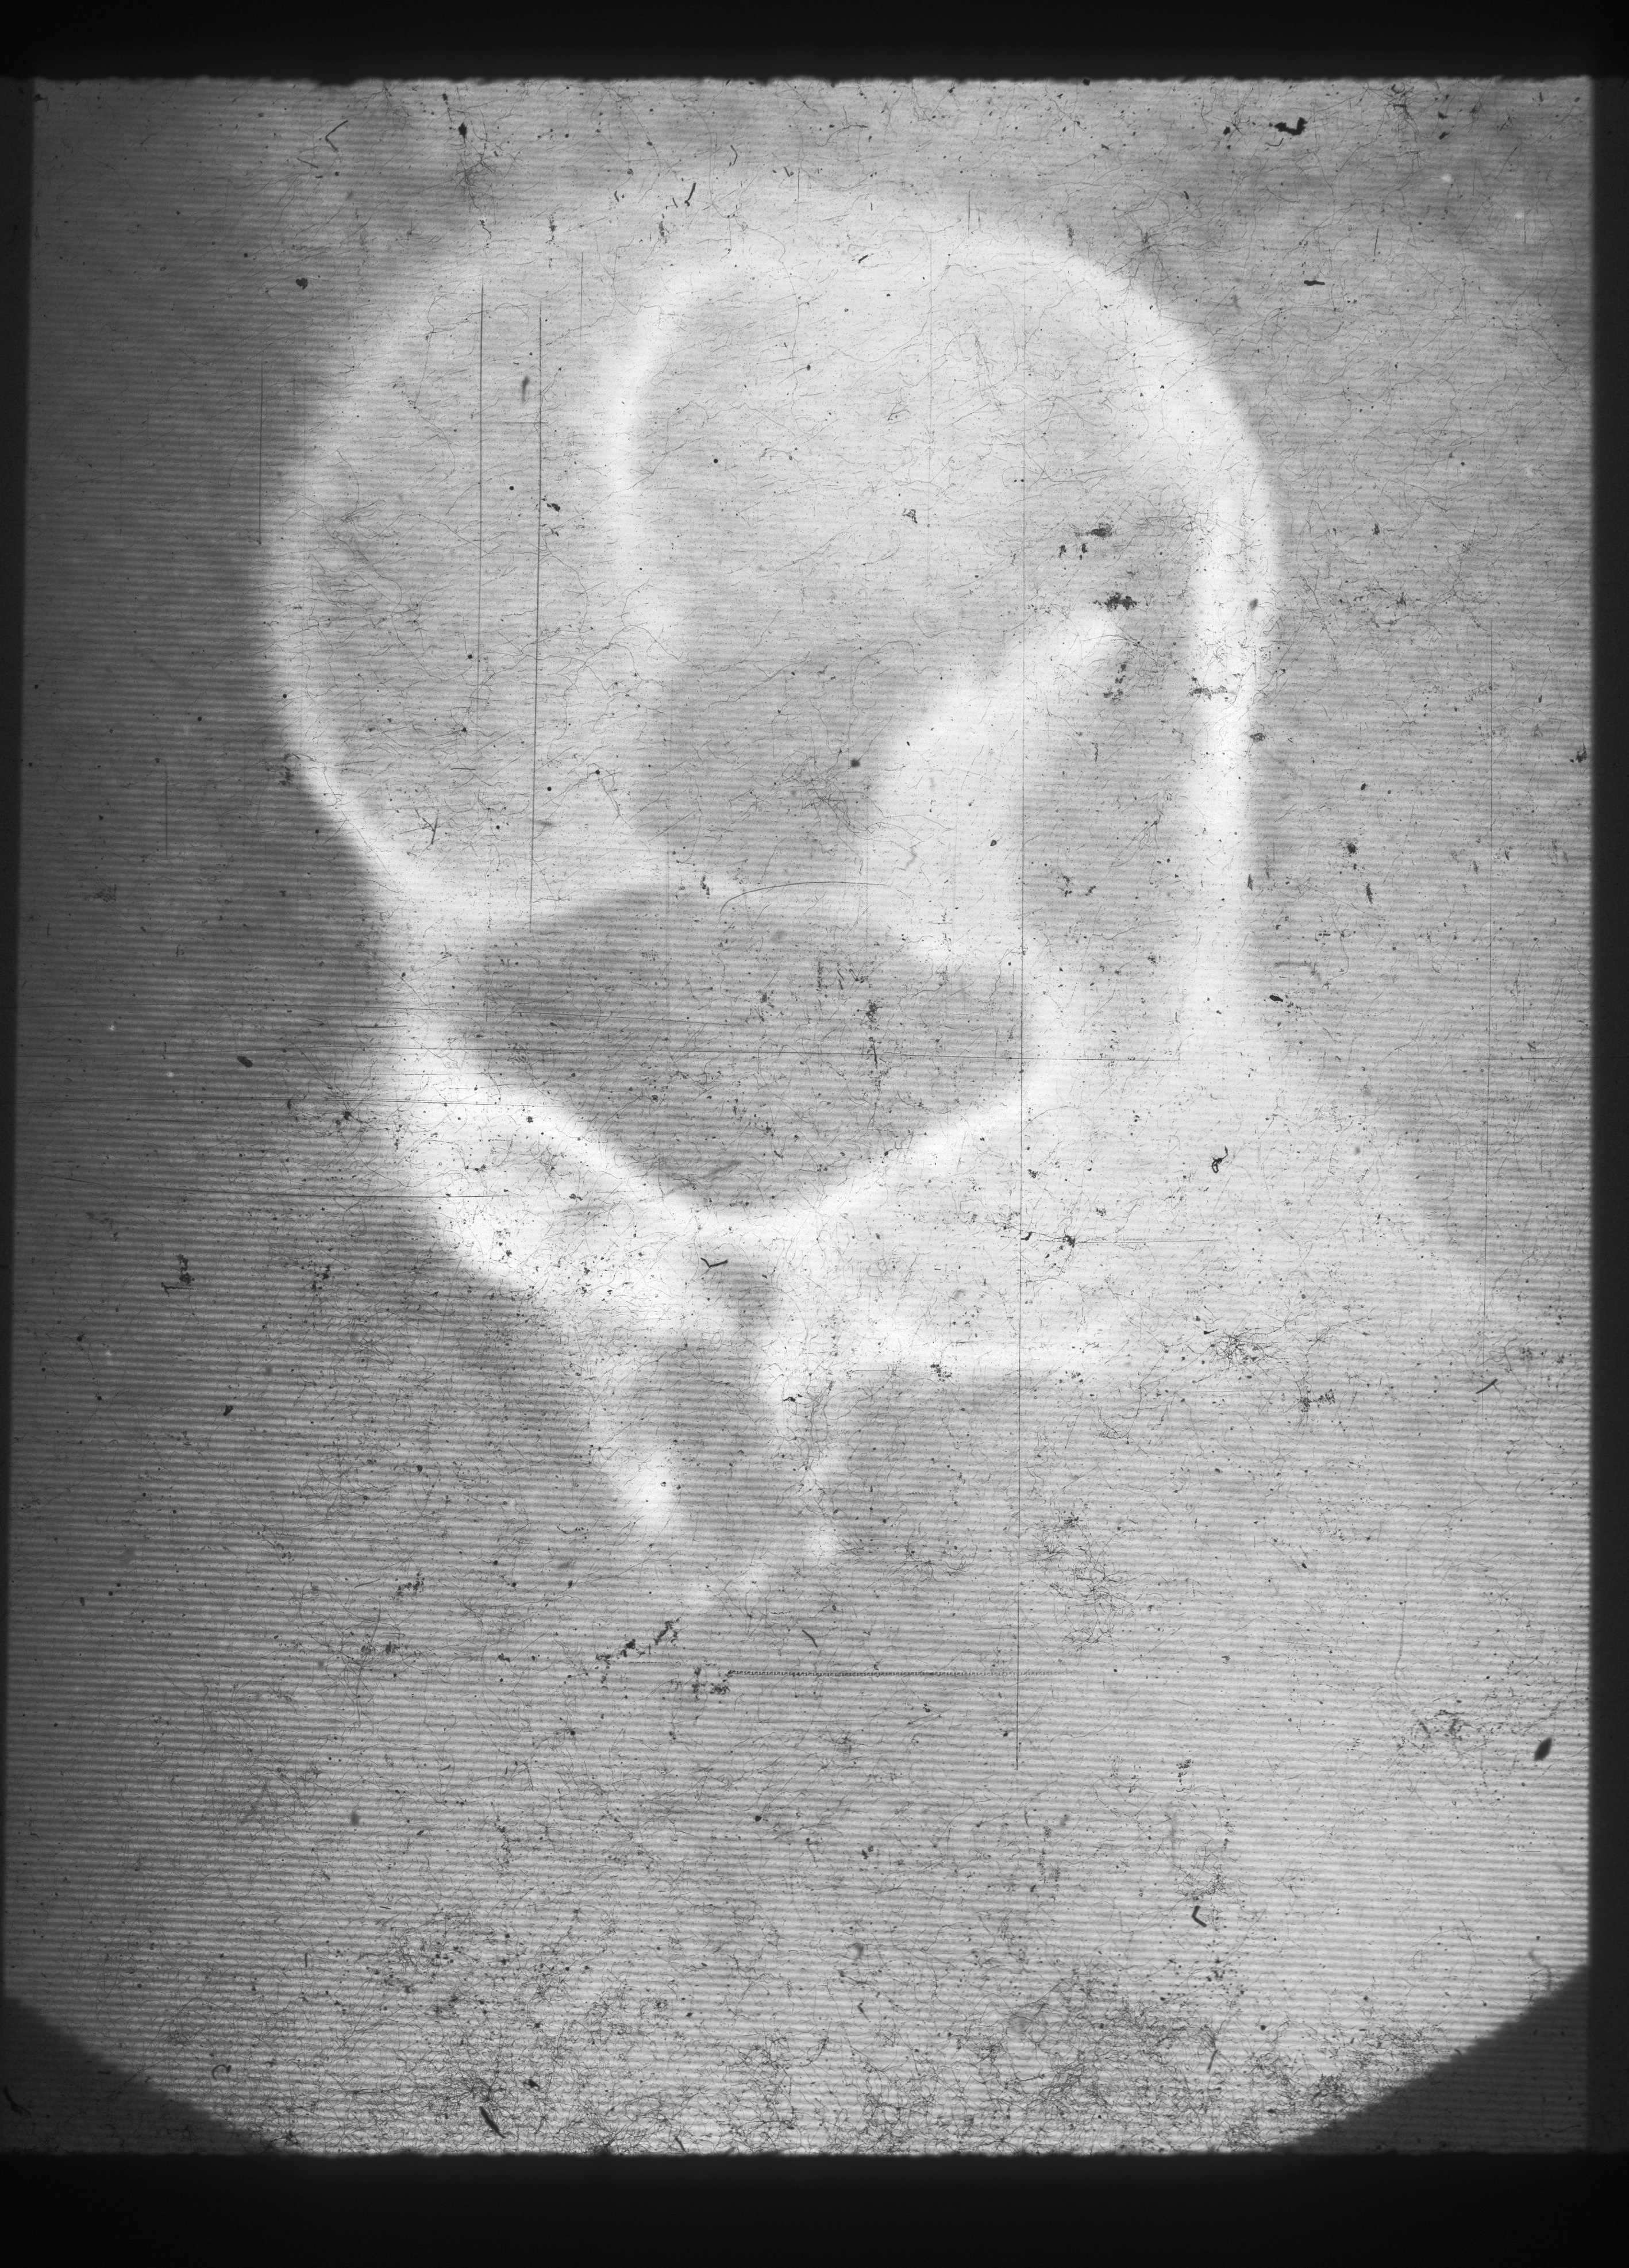

The vault of the skull shows a large lytic lesion containing islands of bone surrounded by sclerotic bone. This is often misdiagnosed as Paget’s disease (Figure 6).

Figure 6: FD skull – sclerosis of the base of the skull with islands in the vault simulating Paget’s.